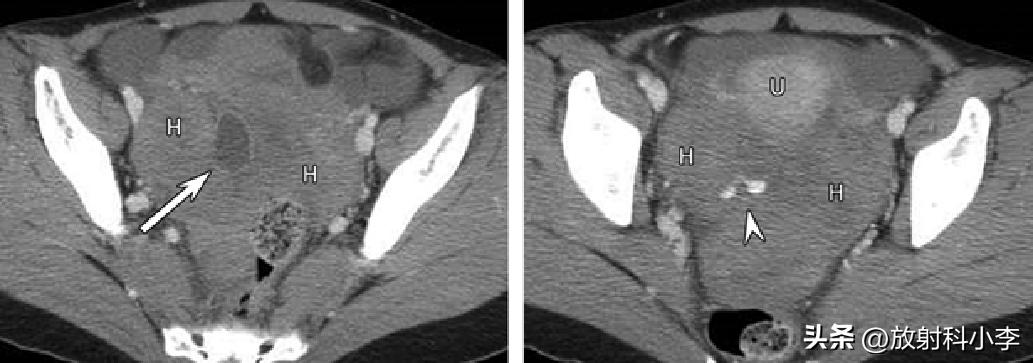

F,30Y,右侧卵巢囊肿破裂,增强CT示右侧附件区卵圆形囊性低密度影,囊壁强化,囊壁不完整,周围见稍高密度积血;另可见对比剂外渗(箭头)。

case 1. F,42Y,突发右下腹痛半天

CT:右侧附件区见一混杂密度肿块,可见脂肪密度,肿块壁增厚,与子宫之间的连接结构增粗、稍扭曲,密度不均匀。考虑右卵巢畸胎瘤蒂扭转。

case 2. F,84Y

3年前的CT平扫示:左侧附件区肿块,主要呈实性,平扫密度较高,伴出血;3年后CT示:左侧附件区肿块较3年前明显增大,呈囊实性,实性成分为主,增强强化轻或无,瘤周见条带影/团块影与子宫相连。